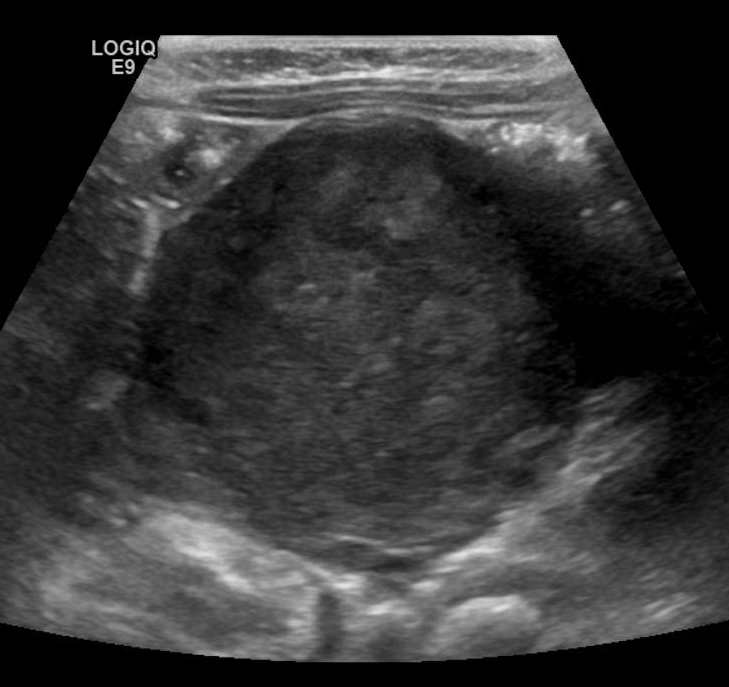

On ultrasound you may encounter a round or ovoid mass with mixed echogenicity often time does the punctate echogenic foci representing classifications.

Retroperitoneal Neuroblastoma